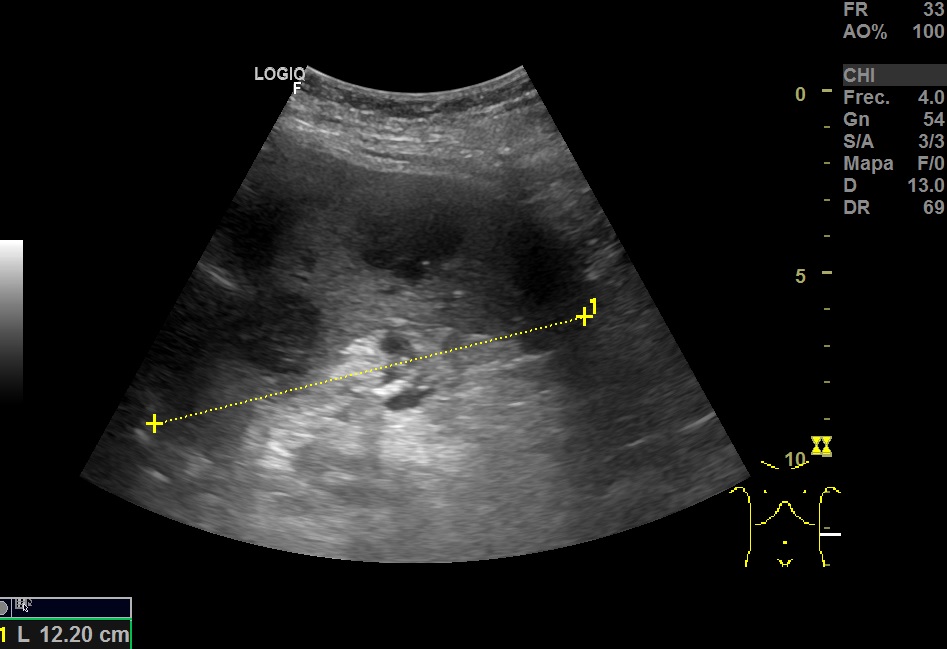

Hallazgos ecográficos

Hallazgos ecográfico: Esplenomegalia y varias lesiones focales hipoecogénicos de diferentes tamaños de bordes bien definidos en el bazo.